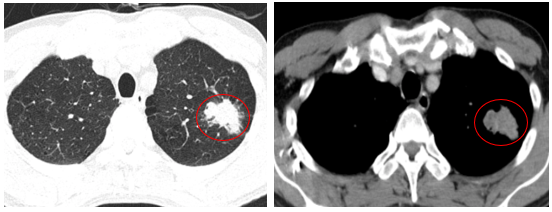

-         Chụp cắt lớp vi tính lồng ngực (06/2025): Nhu mô đỉnh phổi trái có khối tổ chức kích thước ~35x25mm, bờ không đều, có cắt cụt một số nhánh phân thùy đỉnh, ngấm thuốc mạnh không đồng nhất sau tiêm. Thuỳ trên và dưới có nốt đặc nhỏ đường kính 2mm.

Hình 1: Nhu mô đỉnh phổi trái có khối tổ chức kích thước ~35x25mm, bờ không đều, có cắt cụt một số nhánh phân thùy đỉnh, ngấm thuốc mạnh không đồng nhất sau tiêm